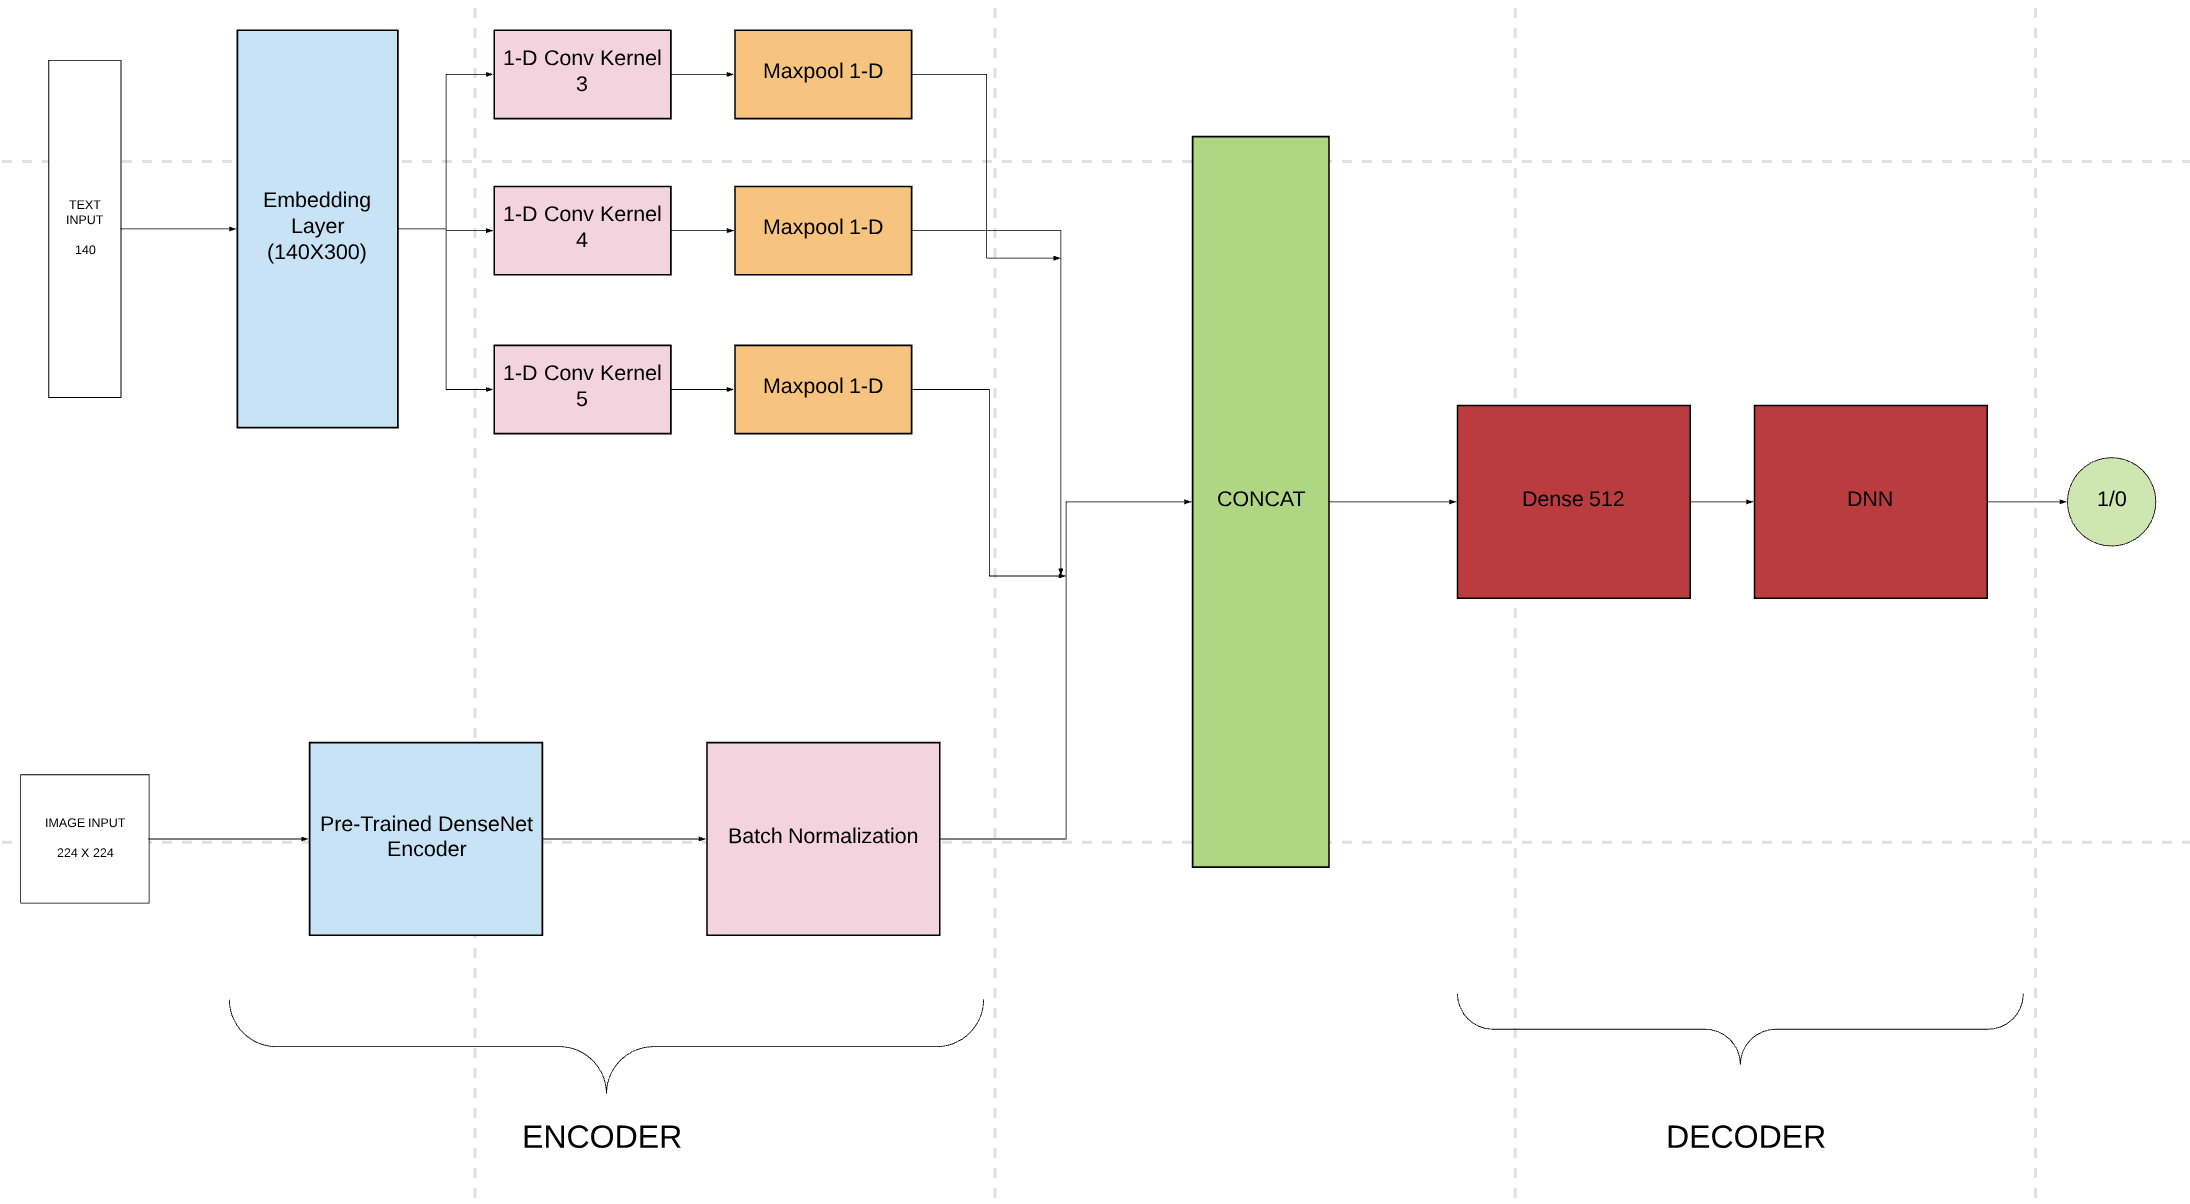

This section focuses on our novel multimodal architecture which consists of a text submodel and an image submodel, as shown in Figure 1. The text submodel is developed by taking the network layers, from input layers to feature vectors, from a trained text classifier. Similarly, the image submodel takes the network layers of a trained image classifier from input layers to feature vectors. Then the encoded text and image feature vectors are concatenated into a single flat feature vector. This feature vector is then passed onto a simple densely connected decoder for the binary classification. Applying transfer learning to the two encoders makes this multimodal function under small data situations. The transferred text and image encoders are the respective pre-trained embedding and residual layers. The pre-training process is described in sections 2.1 and 2.2. These pretrained encoders are then finely tuned on low learning rates.

We choose a CNN based text classifier (Kim, 2015) to meet this task. We also extend the 1-D CNN for classifying short e-commerce product descriptions (Eskesen, 2017) to our text classifier. Resemblance in structure of product descriptions, features of short radiology reports (27.4 words per case on average) are extracted by the Word2Vec approach (Mikolov, 2013). Each document is cut off in 140 words, or padded if a given document is shorter than 140 words. In the spirit of transfer learning, different pre-trained word embedding layers are experimented on, and these are reported in the experimental results (see Table 1 and 2). The eventual text classifier architecture utilizes pre-trained embedding layers specific to the text dataset that is being classified. The choice of a domain specific embedding layer rather then a generalized one is to achieve a clear boost in performance. As stated earlier, the corpus is domain specific and institution specific. Kernels used in the 1-D CNN are of length 3,4 and 5 and the pre-trained embedding layer is not frozen.

The image submodal is centered around the idea of transfer learning. CNN encoders pre-trained on ImageNet and National Health Institute’s ChestX-ray14 gave several different experimentation combinations with diferent encoders (VGG, DenseNet, ResNet, etc.). The DenseNet121 (He et al., 2015) pre-trained on ChestX-ray14 was chosen as the encoder due to its superior accuracy. This encoder is then fed into a simple batch normalization which is then fed into a simple image decoder for binary classification.